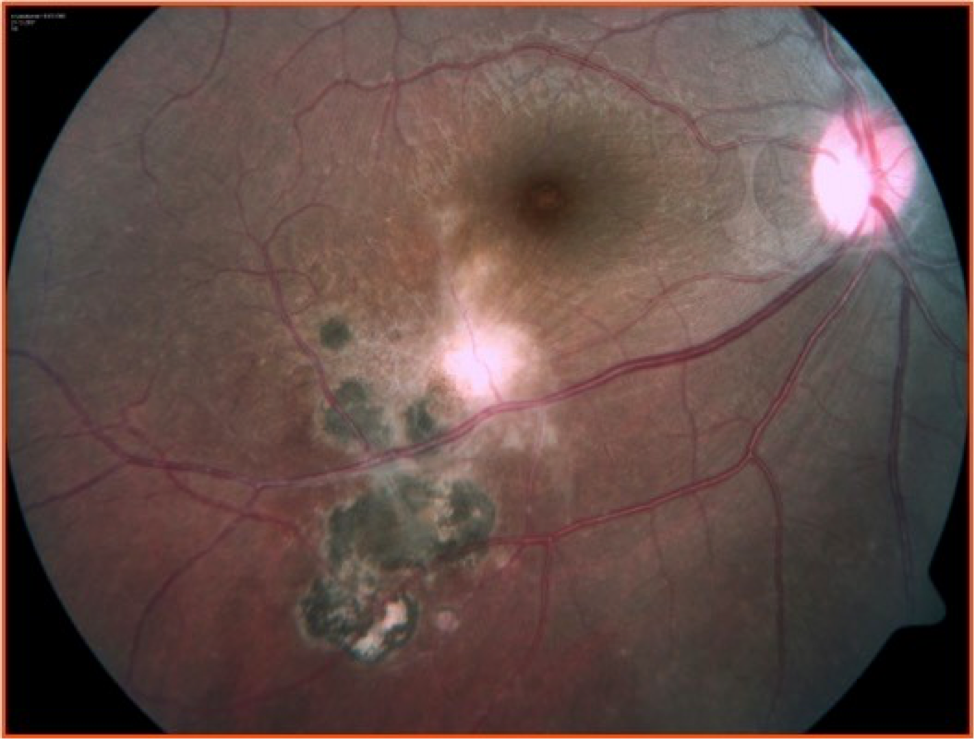

Toxoplasmosis Gondii Chorioretinitis

Toxoplasmic chorioretinitis - Wikipedia A typical chorioretinitis by toxoplasma Ocular Toxoplasmosis: Overview, Pathogenesis, Congenital Versus ... Toxoplasmosis - EyeWiki Fundus photograph of left eye showing active chorioretinitis of ... Toxoplasmosis Gondii Chorioretinitis